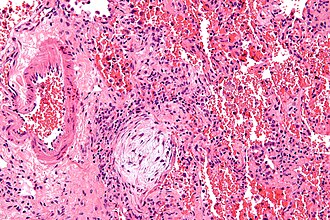

Masson body. H&E stain. | |

- Distal airway disease -- airways plugged with organizing exudate ("Masson bodies").

- "Organized exudate" = fluffy light-staining paucicellular regions with stellate cells (fibroblasts & immature connective tissue).

- No hobnailing of pneumocytes.

- Type 2 pneumocytes hyperplasia is absent.